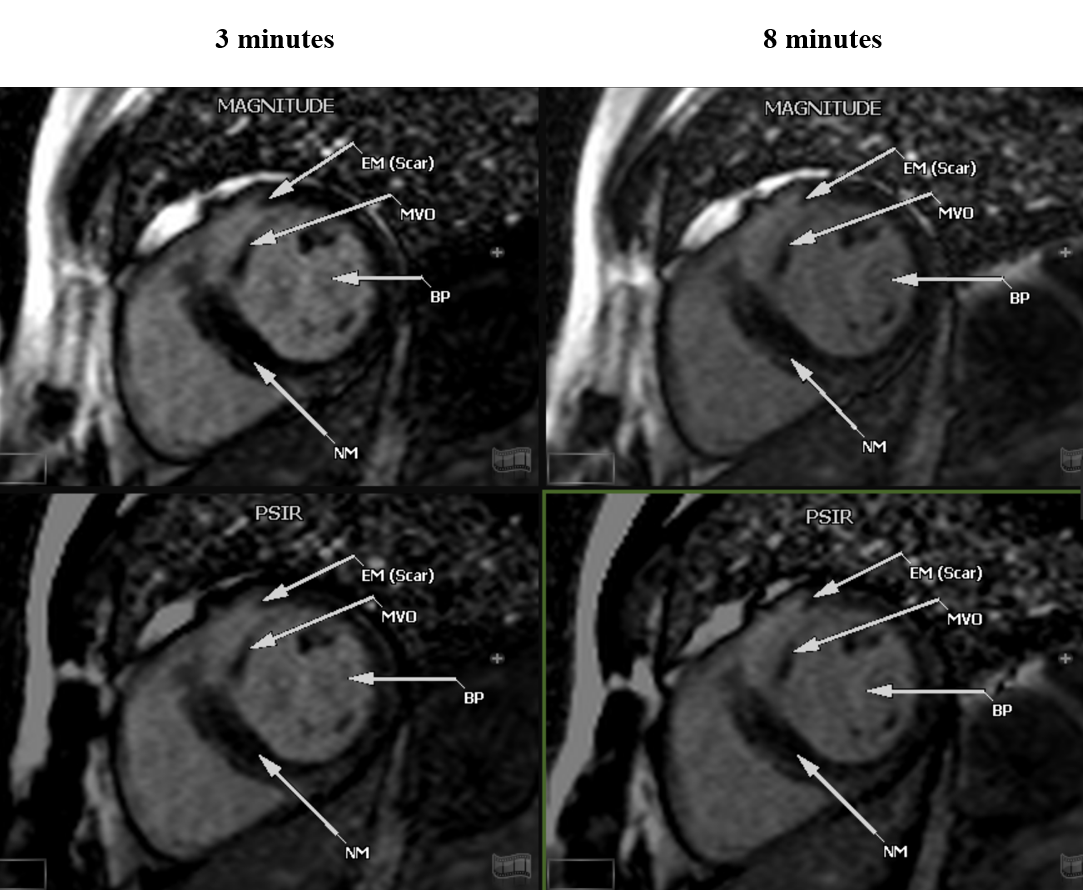

Enhanced Myocardium (EM)

Normal Myocardium (NM)

Blood pool (BP)

EM-NM

BP-NM